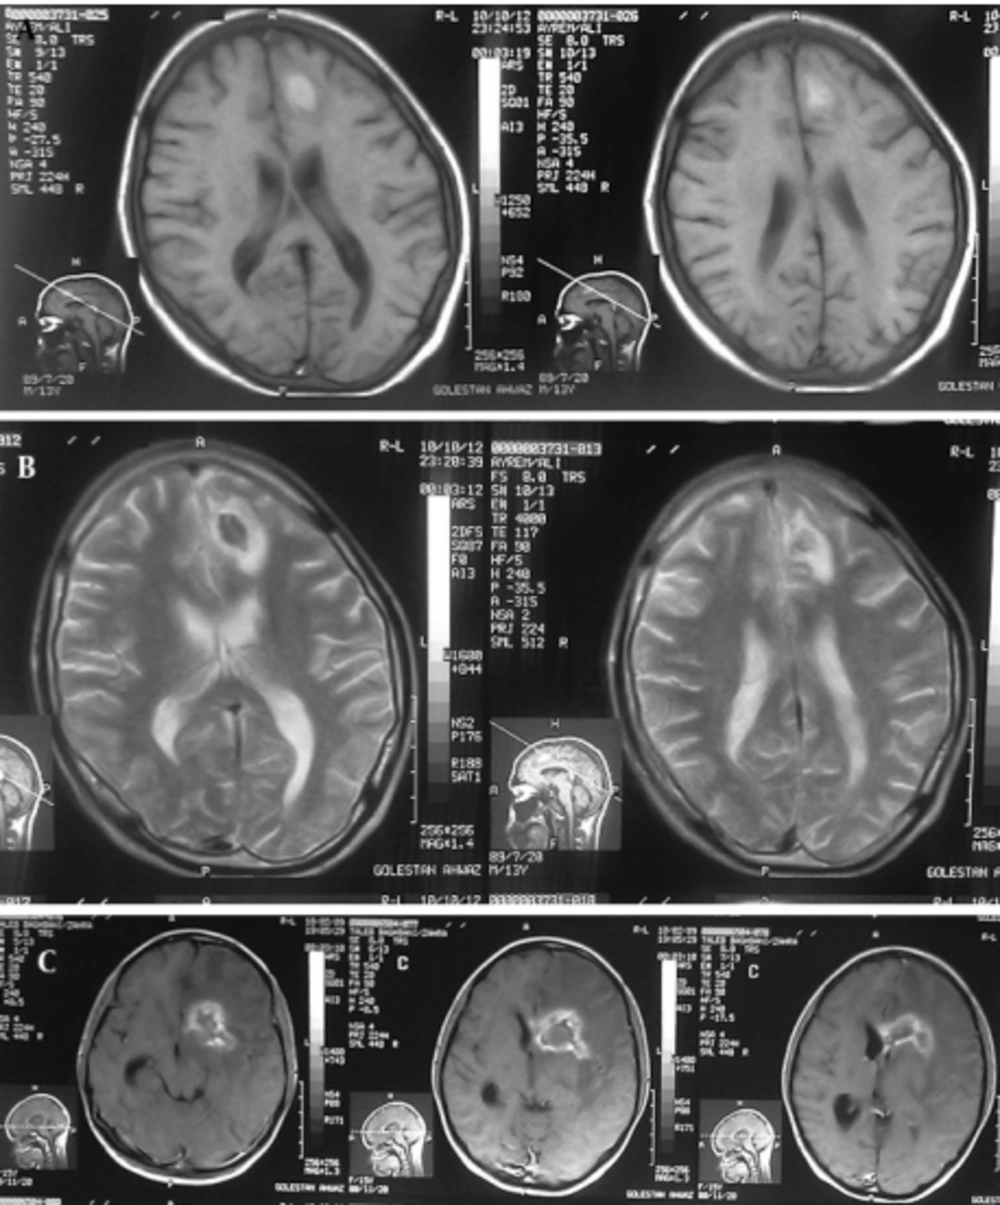

Case 1: A 15-year-old girl with acute lymphoblastic leukemia diagnosed in 2010 was receiving maintenance treatment. Three weeks ago, she referred to a hospital with headache, nausea and vomiting. CT scan of the brain demonstrated low density of mass like a lesion of the left parietal lobes cortico medullary junction accompanies with mild vasogenic edema and no enhancement after contrast media administration. Findings were non specific in CT scan. MRI was applied and on the obtained images there was left parietal corticomedullary junction intermediate signal intensity lesion with vasogenic edema on T2 which as a bright intermediated signal in T1 and low signal intensity peripheral edema (Figure 1A, 1B), follow in contrast media administration remarkable enhancements of lesions are seen (Figure 1C). These findings were compatible with toxoplasmosis and lymphoma. MRI spectroscopy (MRS) was done and increasing of lactate and lipid and low choline were seen in the spectrum of MRS which are specific for necrotizing abscess (Figure 2). Ig M antibody against Toxoplasma by Chemiluminesans (Roche kit) was 8 IU/mL (reference range: non reactive < 0.8; intermitant 0.8- 1; reactive > 1) and Ig G was 4 IU/mL (reference range: Non reactive ˂ 1; intermitant 1- 3; reactive ˃ 3). The patient prescribed with pyrimethamin, sulfadiazine and leucoverin.

A: T1- Weighted axial MRI: Left parietal corticomedullary junction, bright intermediated signal and low signal intensity peripheral edema. B: T2- Weighted axial MRI: Left parietal corticomedullary junction, intermediate signal intensity lesion with vasogenic edema. C: MRI with contrast shows remarkable enhancement of lesions.